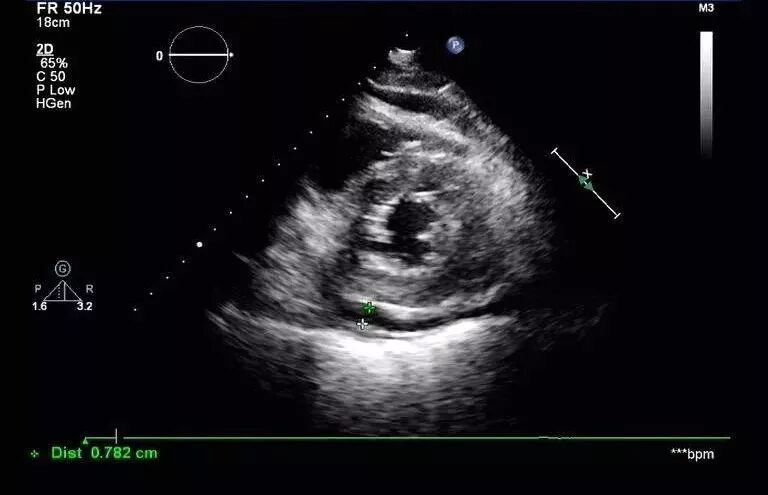

图5: 2017年8月30日复查经胸超声心动图提示:左室靠近心尖处血肿形成。少量心包积液。左室靠近心尖处外壁可见一低回声包块,大小约40mmx21mm,边界尚清。

图6 :心包腔见液性暗区,右室前壁4mm,左室后壁5mm。